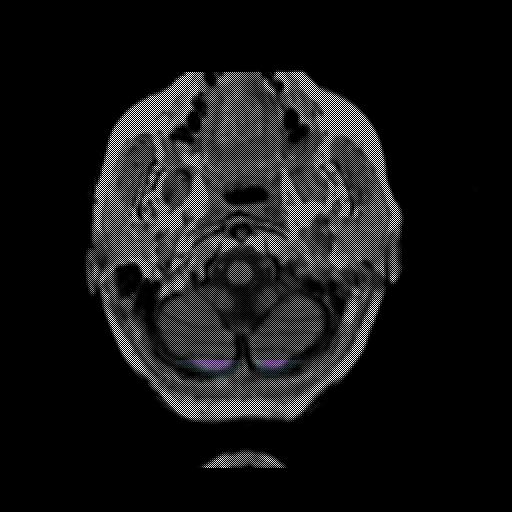

overlay: Slice 5

Slice 5

MRCBFCBF with

T1PDT2T1PDT2